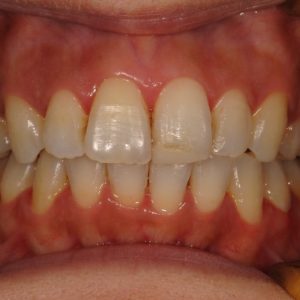

虫歯の治療、矯正の相談をご希望され来院されました。お口の中を診査(レントゲン写真、口腔内写真、視診)させていただいたところ、虫歯については問題なくきれいに歯磨きされているようでした。 正面から見るとジグザグしており、お口 […]

全体的な歯並びの矯正治療を行いました。治療期間は3年間。

ジグザグの歯並びを気にされてご来院されました。. 見た目の問題も大切ですが、それ以上に清掃がしにくいために虫歯・歯周病に非常になりやすく、不正咬合(良くないかみ合わせ)は顎の関節に負担をかけてしまい顎関節症を引き起こす可 […]

歯の大きさに対する顎の大きさのスペース不足により歯が並びきらず、ジグザグの歯並びおよび上の前歯が出っ歯になっていました。 左右4番の歯を抜歯することにより歯を並べるスペースを確保し、歯並びを揃えました。 全体の歯並びが綺 […]